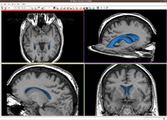

CompareView for Longitudinal Visualization of MS implemented by Jim Miller and demonstrated using a set of 5 scans of a patient with multiple sclerosis. Data provided by Dominik Meier of the Center for Neurological Imaging